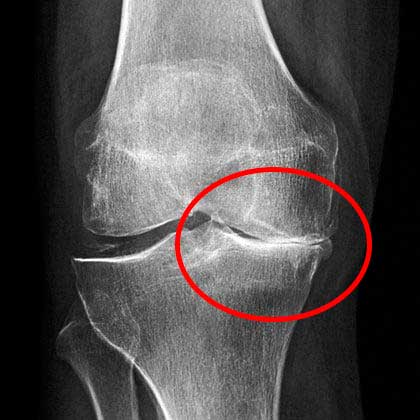

राजेश के जोड़ो की तस्वीरें देखें, जब मैंने उसे उपचार देने से पहले देखा था:

📌यहां स्पष्ट रूप से देखा जा सकता है कि नमक ने गलत उपचार के कारण जोड़ को पूरी तरह से नष्ट कर दिया।

यहां स्पष्ट रूप से देखा जा सकता है कि नमक ने गलत उपचार के कारण जोड़ को पूरी तरह से नष्ट कर दिया। कुछ ही समय में, बड़े टुकड़े ओर्थोसोले को आसानी से हड्डी का बड़ा हिस्सा तोड़ सकते थे, जिससे राजेश को जोड़ के पूरी तरह से खराब होने और स्थायी विकलांगता का सामना करना पड़ता।

बस इन परिणामों को देखिए, इससे पहले और बाद में।